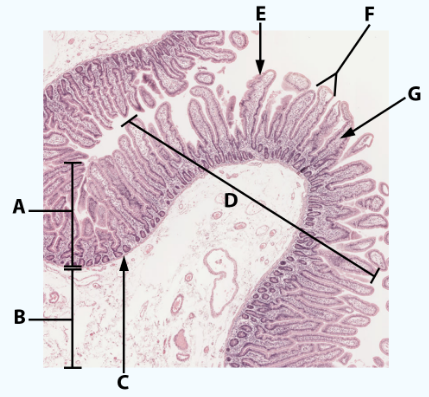

A

Serosa

B Esophagus

Muscularis externa: skeletal, skeletal/smooth, and smooth, circular and longitudinal

B Stomach

Oblique, circular, and longitudinal smooth muscle

B Small intestine

circular and longitudinal smooth muscle

B large intestine

circular and longitudinal smooth muscle

C

Submucosa: areolar and dense connective tissue

D

Lumen

D1

Gastric glands/pits

D2

Villi of small intestine

D3

Intestinal crypts of large intestine